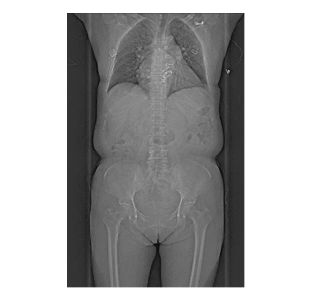

支持“無禁忌”全身檢查,尤其適合急癥患者(如急性胸痛、胸痛三聯(lián)征)的“一站式”快速檢查,為搶救贏得黃金時間。

輻射劑量僅為傳統(tǒng)CT的1/5,一次肺篩查劑量低至0.06mSv(相當(dāng)于一張胸片),集團(tuán)醫(yī)院設(shè)有專門的兒童低劑量肺CT檢查,可使兒童、體檢人群及需多次復(fù)查的患者更安心。

1.心腦血管疾?。?.14秒完成心臟掃描,冠脈成像不受心率限制,也同時支持心肌灌注評估。 2.腫瘤診療:雙能量技術(shù)助力良惡性鑒別、療效監(jiān)測,實現(xiàn)腫瘤體積、密度的動態(tài)追蹤。3.神經(jīng)系統(tǒng)檢查:對于腦外傷、出血、腫瘤等疾病的診斷,可提供高質(zhì)量的圖像,幫助醫(yī)生準(zhǔn)確判斷病情。雙能量活動性腦出血分析和神經(jīng)灌注檢查,有助于評估腦卒中缺血半暗帶,為臨床治療決策提供重要參考。 4.急診與重癥:1秒全身成像快速排查多發(fā)傷、肺栓塞等急危重癥,縮短檢查時間。